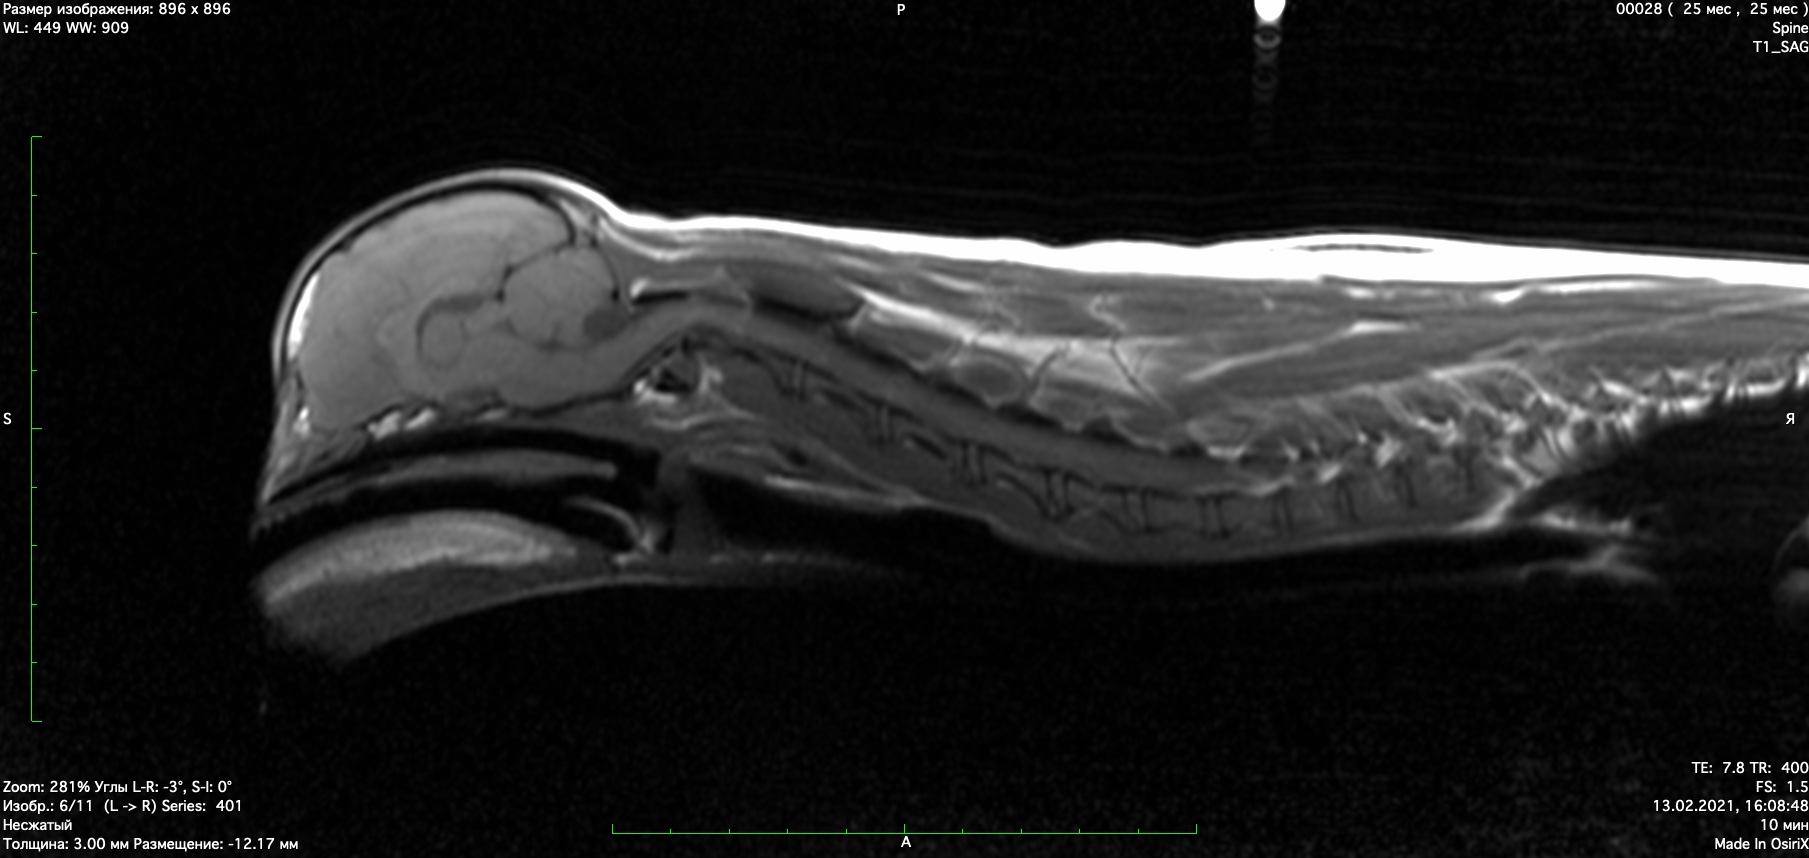

При проведении мрт диагностики установлено смещение второго шейного позвонка с компрессией спинного мозга, аплазия зуба второго шейного позвонка